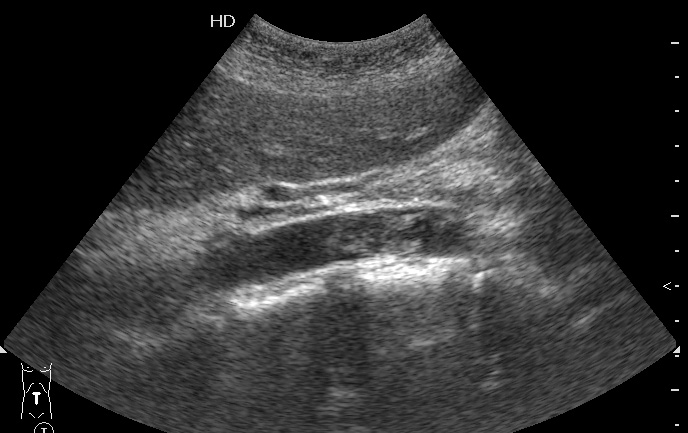

УЗИ: тромбоз инфраренального отдела аорты

Пожилая женщина, поступила в БСМП с резкими болями в ногах. Пульс на бедренных артериях отсутствует.

Продольный скан аорты

Назначено консервативное лечение, назавтра появился кровоток в бедренных артериях.